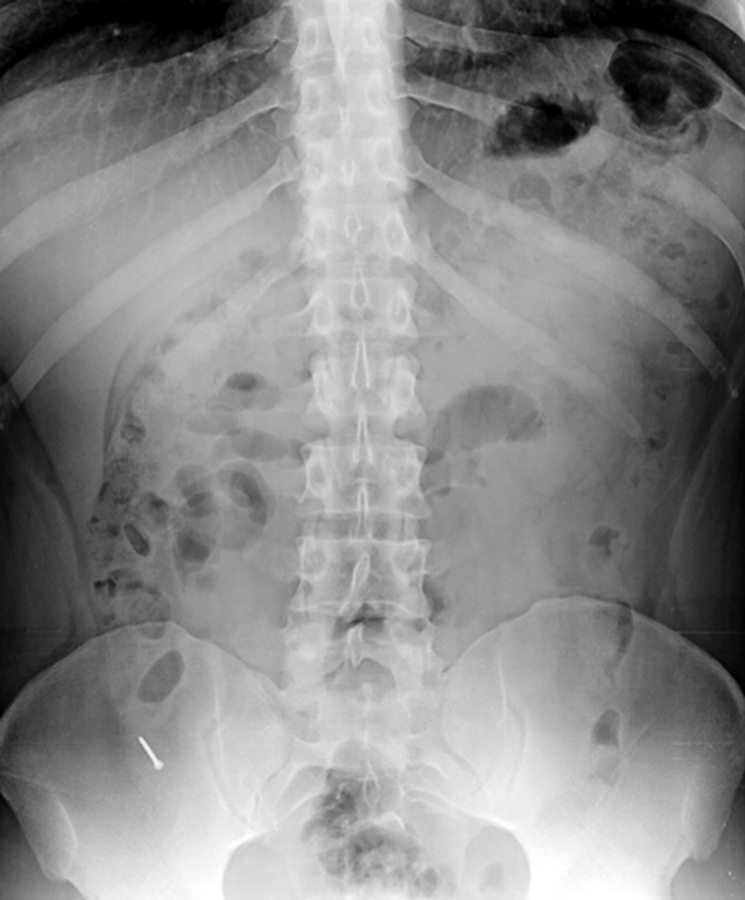

Nachdem es nicht gelungen war, den 3 cm langen Nagel endoskopisch zu bergen, entschieden sich die Ärzte für eine Appendektomie. Nachdem es nicht gelungen war, den 3 cm langen Nagel endoskopisch zu bergen, entschieden sich die Ärzte für eine Appendektomie. © Cevallos JM et al. Jour Surg Case Rep 2019; rjy335

Die Kollegen aus Ecuador versuchten zunächst, den Fremdkörper koloskopisch zu entfernen. Mit der Glasfaseroptik drangen sie auch bis zur Appendix vermiformis vor, aber der Nagel war darin nicht aufzufinden. Also wurde die Präsenz des spitzen Metallkörpers mit einem intraoperativen Röntgenbild gesichert und der Wurmfortsatz samt unerwünschtem Inhalt chirurgisch entfernt. Der weitere Verlauf war komplikationslos.